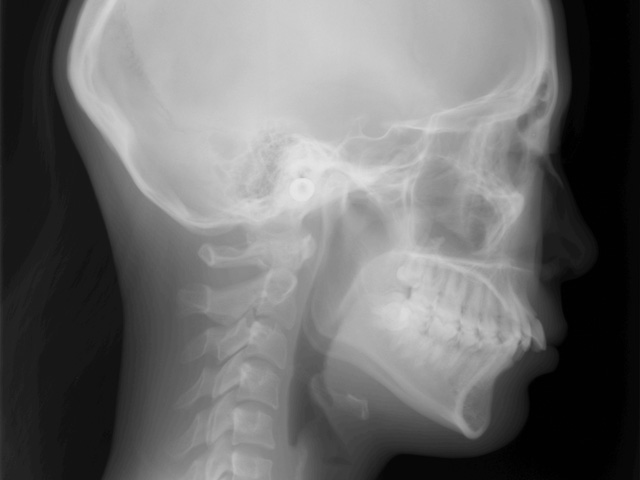

セファロレントゲンの側方画像です。

レントゲン画像に写り込んでいる鼻と上下口唇のバランスは悪くありません。

ただし、上の前歯はいわゆる「出っ歯」と呼ばれる状態で、明らかに改善が必要です。